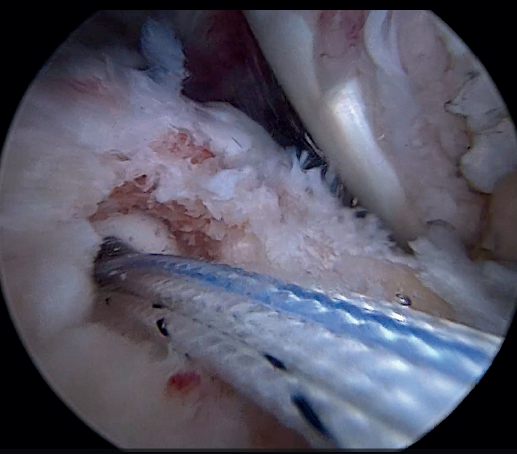

The greater tuberosity is then prepared with the bone drill, creating a bleeding bone surface to enhance tendon-bone healing, as this is where both cuff repair and augmentation with biceps will be carried out (Figure 1).

Previously, at intra-articular level, we assessed the quality of the LPB and its insertion in the supraglenoid tuberosity; from subacromial, having prepared the bony footprint on the greater tuberosity, we proceed to release the proximal portion of the tendon from the bicipital groove. The upper part of the transverse humeral ligament is sectioned to mobilize the LPB without damaging it (Figure 2). At this time, the mobility and integrity of the LPB is checked with tendon pulling forceps (Figure 3).

The glenoid origin of the LPB is preserved at all times. In the anterolateral zone of the greater tuberosity, we implant an anchor loaded with three sutures (FiberTak® 2.6 mm, Arthrex, Naples, FL, USA), more medial to the reflection zone of the LPB. To ensure correct guidance at implantation, we create a superolateral accessory portal without a cannula, close to the limit of the acromion.

Using penetrating forceps through the anterior portal, the surgeon penetrates the LPB and retrieves one of the suture threads, performing a self-locking Lasso suture in the same step. This is done with two of the three anchoring threads to ensure a correct LPB grip to the footprint of the greater tuberosity and that the tendon does not fray; we do not cut the two threads after knotting (Figures 4, 5 and 6). We also consider it very important to apply the biceps tendon, keeping it as flat and anatomical as possible, avoiding twisting or excessive distension of the tendon. Subsequently, a tenotomy of the LPB distal to these sutures is performed (Figure 7), thus allowing the LPB to function as a superior capsular reconstruction, restricting the ascent of the humeral head.